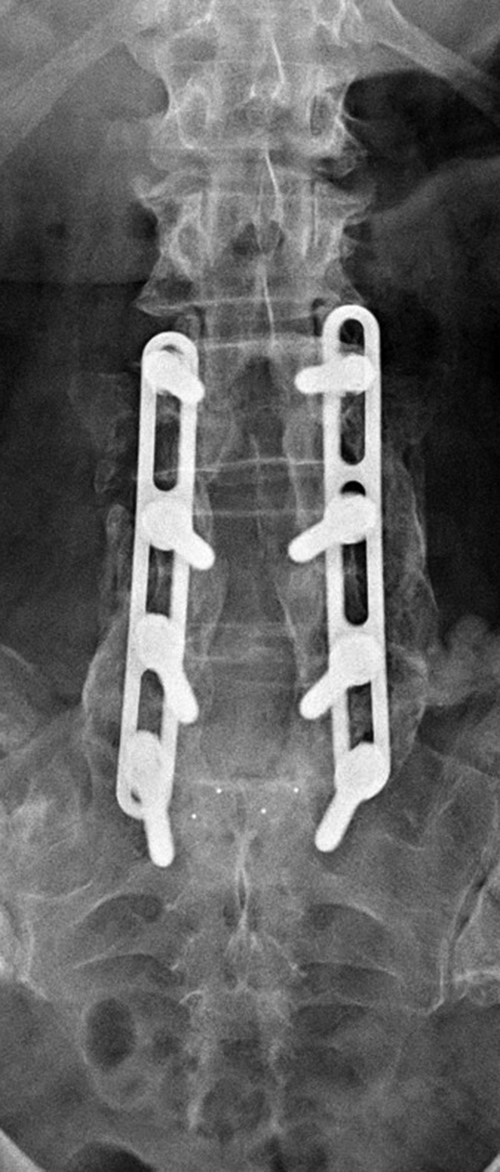

| Harms vertebral cage (AP view) |

Lumbar spine bony disk strut, pedicle screws, and pedicle rods (AP view) |